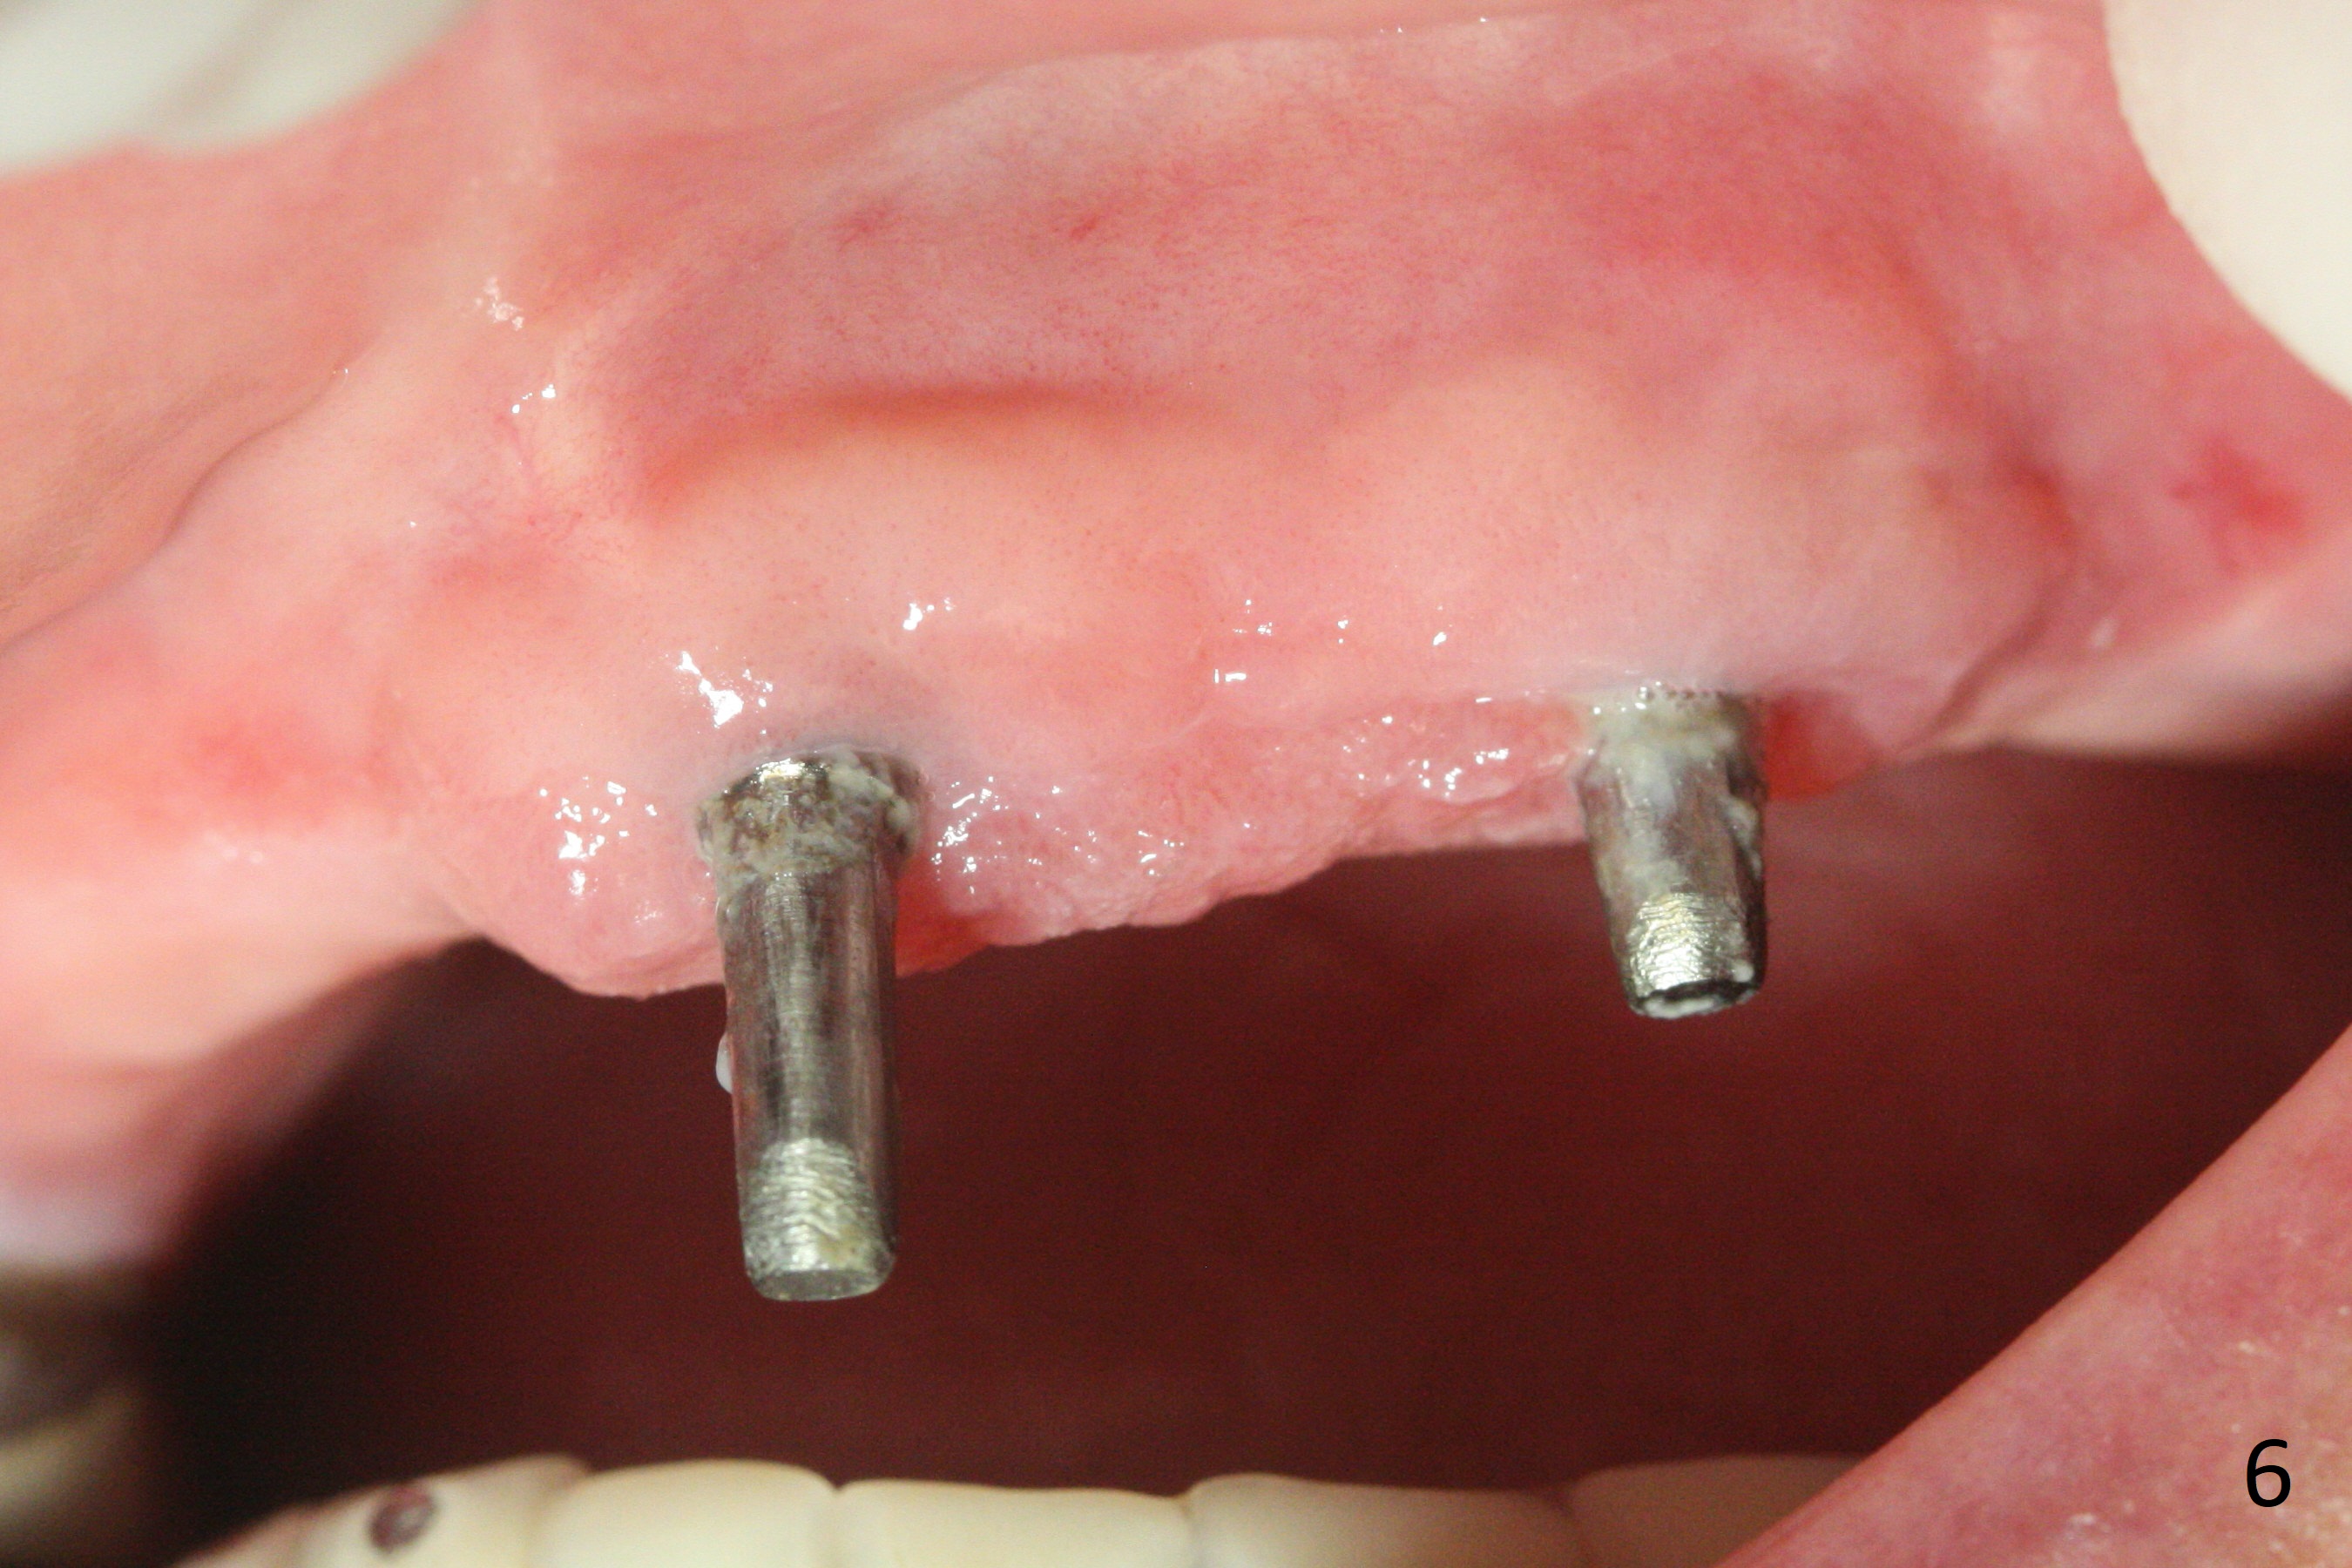

Incision reveals that the ridge at #9 and 11 is narrower than expected. A 3x14 mm 15º 1 piece implant is placed at the site of #9, while a 3x17 mm straight 1-piece one is placed at #11 (Fig.1,4). Insertion torques at #9 and 11 are 20 and 30 Ncm, respectively. The relatively low insertion torque is partially due to osteoporosis. The 65-year-old lady also has dry mouth. Osteotomy should be underprep. The position and trajectory of the implants are dictated by the partial denture (Fig.2). After minor abutment adjustment (Fig.3), an immediate provisional bridge is fabricated. There is no interference when the partial is removed and inserted. After bone graft (Fig.4 ^) and Osteogen Membrane, the ridge (Fig.3) is wider than before. The patient returns for reline 2 months postop (Fig.5-7). In spite of insufficient oral hygiene, the gingiva remains healthy around the implants. To form distinct papillae, acrylic should be added to (Fig.8 yellow line) and removed from (hushed area) the individual provisional crowns. One month after provisional modification (Fig.10, as compared to Fig.5), the pontic recipient site is concave (Fig.11) and becomes less concave after cord packing and abutment trimming. When the provisional bridge is reseated after impression (Fig.12), the pontic recipient site must be blanched again. Please trim the pontic recipient site of the model ~ .5 mm to enhance cosmetics. Water Pik has been used since surgery, but it may be related to loss of bone graft 3.5 months postop (Fig.9 *). One month post cementation, the patient has complained of pain when water pik is irrigating the gingiva palatal to the FPD, apparently in association with denture-related Candidiasis. Two weeks of use of Mycostatin Oral Suspension, peri-implantitis or peri-implant mucositis-like signs and symptoms disappear (Fig.13). CBCT taken 6 months postop confirms that the implants appear to be have been placed in the bone (14,15). The FPD appears to be loose 2.5 years post cementation.